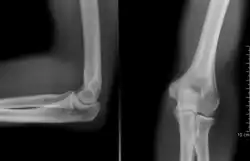

radiographie (coude droit)